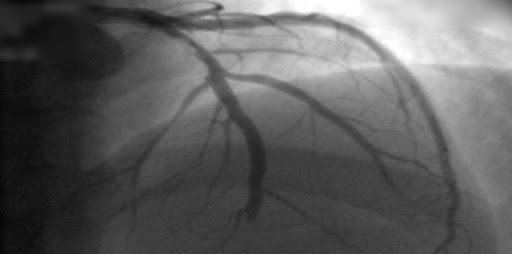

Tomografía computada versus angiografía invasiva en la angina de pecho estable

28 abril 2022

En los pacientes remitidos para cateterismo coronario por dolor torácico estable y con probabilidad intermedia de enfermedad coronaria antes de la prueba, la evaluación inicial por tomografía computada tuvo un riesgo de eventos cardiovasculares mayores similar a los de la evaluación invasiva, pero una menor frecuencia de complicaciones mayores relacionadas con el procedimiento. New England Journal of Medicine, 28 de abril de 2022.